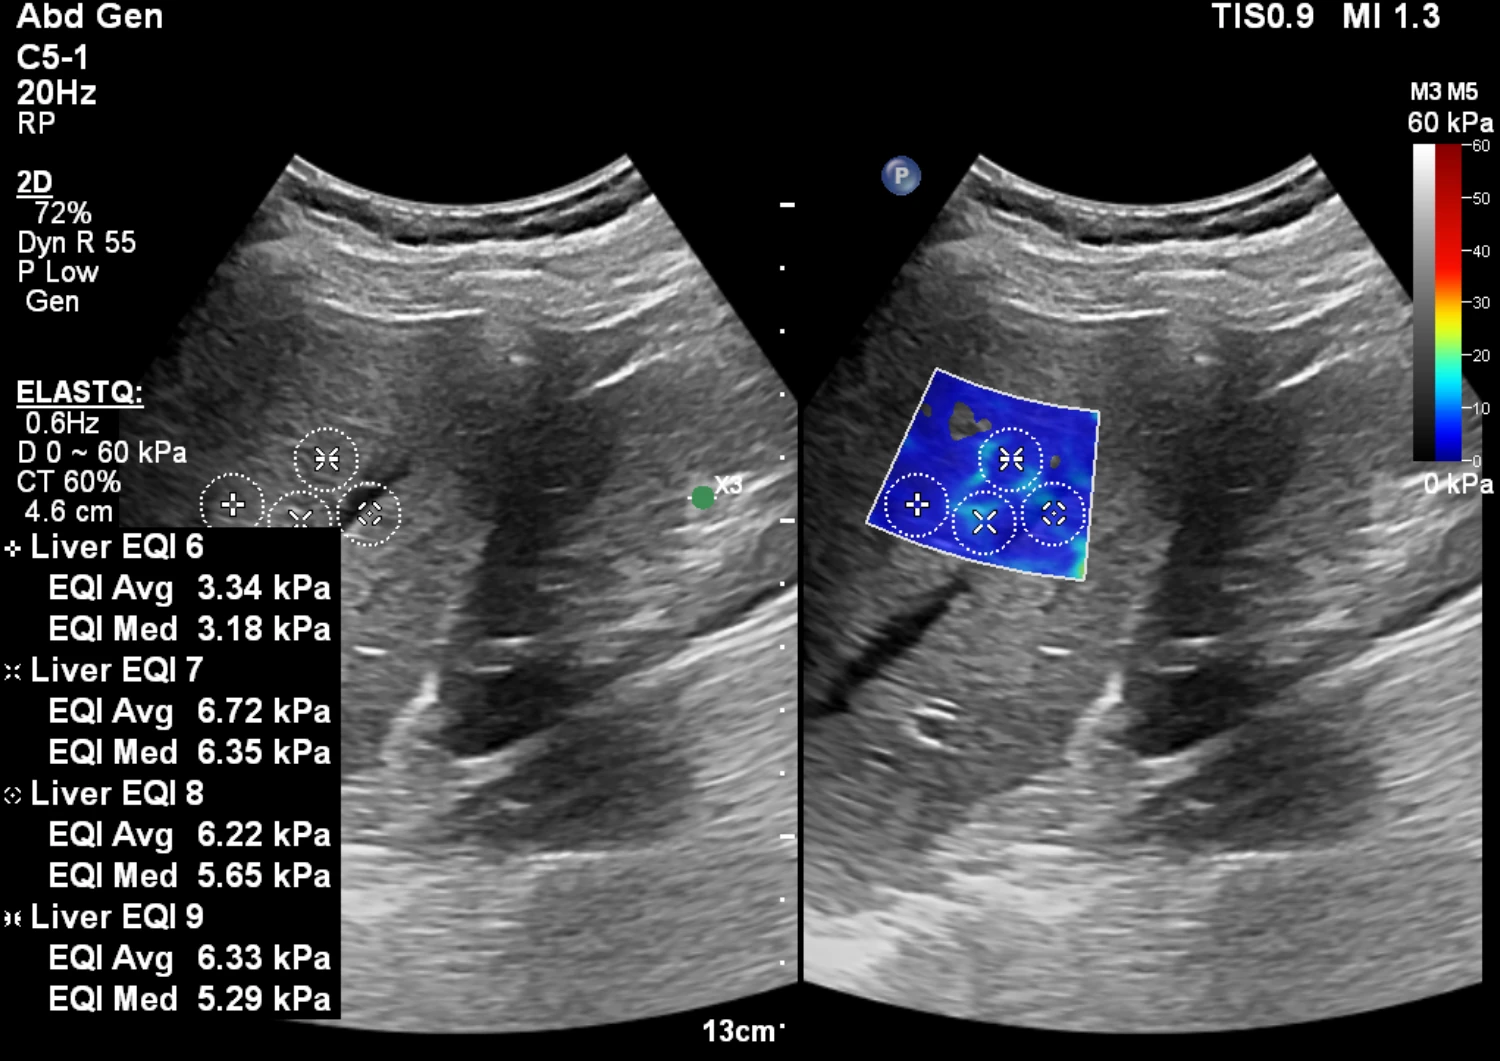

Leber-Elastografie

Mit der Leber-Elastografie messen wir die Gewebesteifigkeit der Leber schnell, schmerzfrei und ohne Strahlenbelastung. Damit lässt sich das Risiko für Leberfibrose und -zirrhose deutlich besser einschätzen als allein mit Blutwerten. In Kombination mit der klassischen Sonografie und Laborparametern ergibt sich ein präzises Gesamtbild – direkt in einer Untersuchung.

Die Elastografie ergänzt die Leber-Sonografie um eine objektive Messgröße: die Lebersteifigkeit (typisch in kPa). So werden frühe Fibrose-Stadien besser erkennbar und unnötige invasive Abklärungen können oft vermieden werden.

Wir führen die Untersuchung mit unserem hochmodernen Ultraschallgerät durch – inklusive optimierter Bildgebung und standardisiertem Messprotokoll für verlässliche Verlaufskontrollen.

Vorbereitung auf die Untersuchung: Idealerweise nüchtern (ca. 3–4 Stunden), da Mahlzeiten Messwerte beeinflussen können.